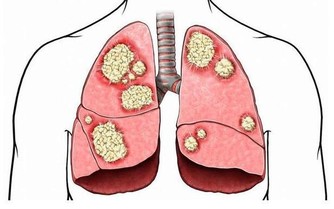

4、患癲癇病

這是一種非常惱人的疾病,雖然不是一直持續,但是一旦犯病也是非常的凶險,患者可能會暫時失去意識,非常容易出意外,而且,這種癲癇是越犯越厲害,研究發現這種癲癇症跟缺鈣也有非常大的關係。